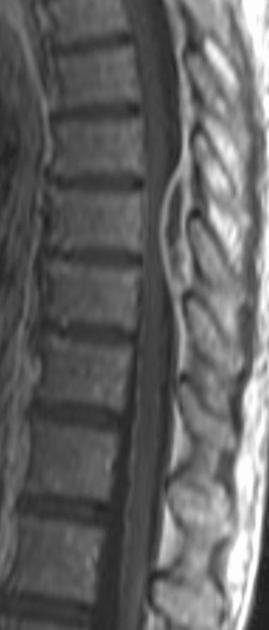

subacute combined degeneration

demyelination of dorsal columns

B12 deficiency, syphilis, copper deficiency, methotrexate toxicity